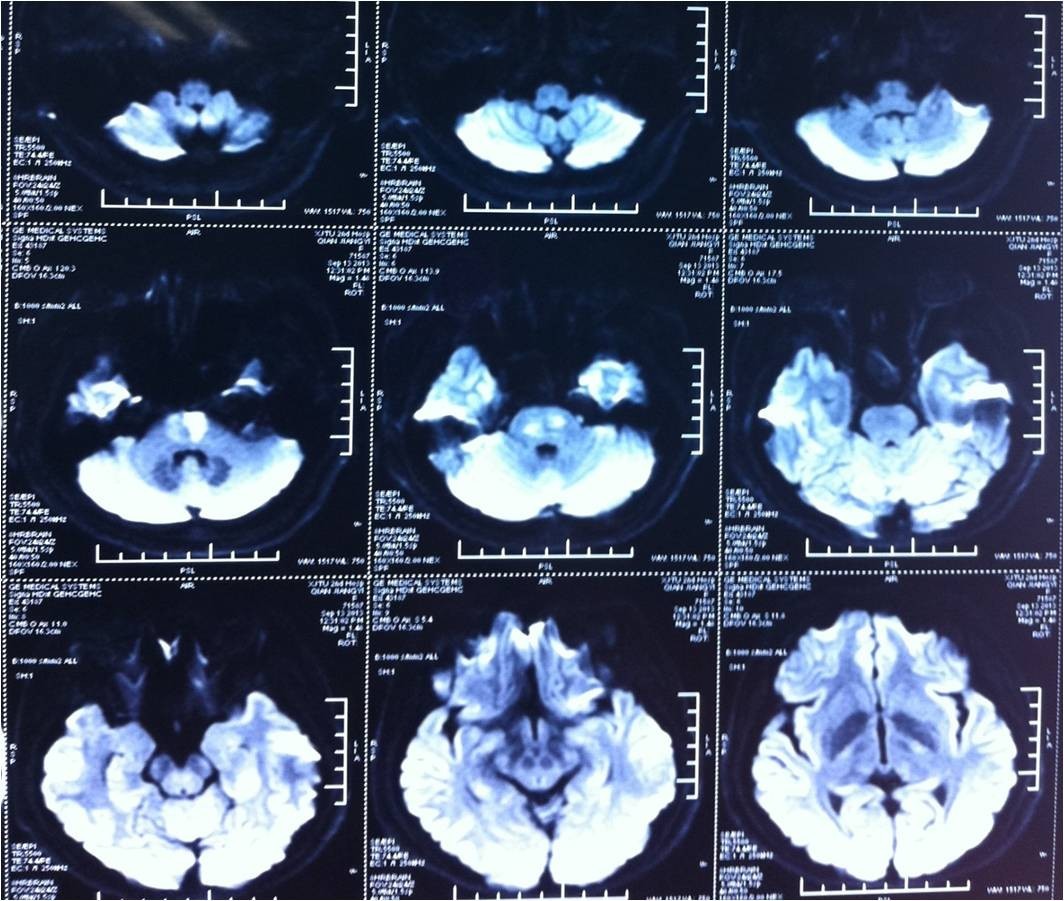

》2013.1-2014.1 ;

》病例数10例,男7例,女3例 ;

》年龄为35-78岁 ;

》合并心房纤颤6例,SIE 2例,不明原因2例 ;

》DSA:大脑中动脉闭塞8例,基底动脉闭塞2例;术后造影示闭塞段血管均无狭窄,排除了动脉粥样硬化所致的脑梗死。